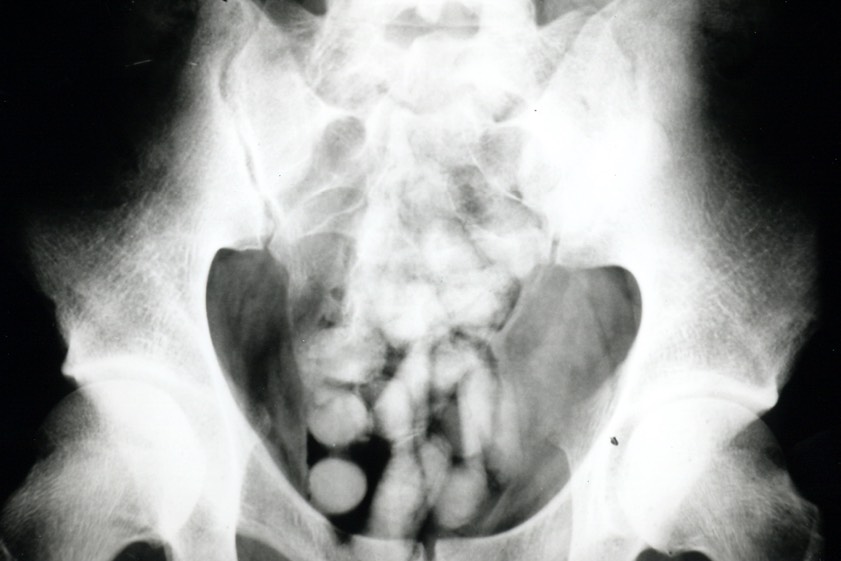

"Bei der Zoll-Kontrolle verstrickte sich der Mann in Widersprüche, was seine Auskünfte über Reisezweck und -dauer anging", wurde heute erklärt. "Die Beamten führten daraufhin einen Drogen-Wischtest durch, der das Kokain anzeigte." Da weder am Körper noch im Handgepäck des Kolumbianers allerdings Kokain gefunden worden sei, habe der Mann im Krankenhaus geröntgt werden müssen. "Das Röntgenbild zeigte Fremdkörper und bestätigte damit den Verdacht der Zöllner", berichtet Marie Müller, die Presse-Sprecherin des Hauptzollamts München.

Als Bodypacking wird das Verschlucken von Betäubungsmitteln zum Zweck des Transports bezeichnet. Die Drogen werden dabei in speichel- und magensäure-resistente Beutel wie zum Beispiel Kondome verpackt. "Platzt nur eines dieser Behältnisse im Magen, bedeutet das in den meisten Fällen den sicheren Tod", betont der Zoll.